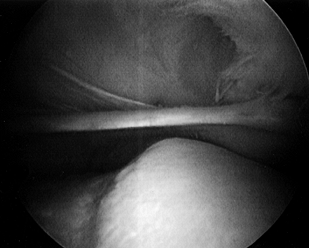

meniscus and the articular cartilage surfaces (Fig. 84.25; see also COLOR FIG. 84.25).

Figure 84.25. (See COLOR FIG. 84.25.) Arthroscopic view of the medial compartment. -